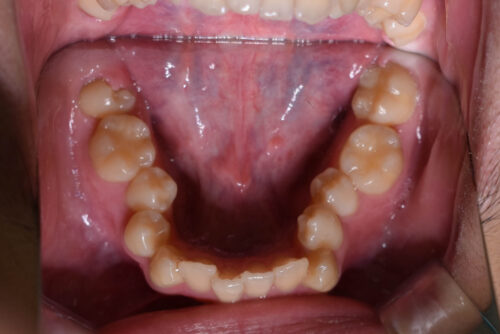

初診時年齢 17歳 男性

歯のでこぼこ (叢生)と

咬み合わせの深さ (過蓋咬合)を

歯のがたつき(叢生)が強く認められ

また下の歯が 全く見えず 過蓋咬合の状態でした。